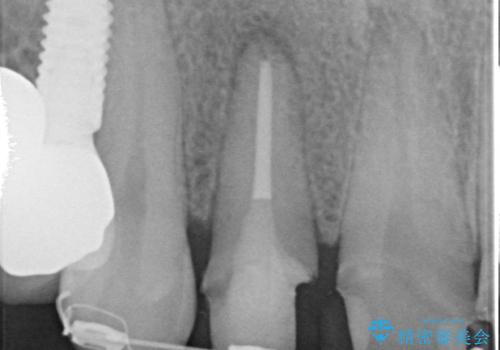

虫歯のマイクロスコープによる丁寧な除去、根管治療、深い虫歯に対する挺出(エクストリュージョン)および歯周外科を行ったのち精度の高いセラミッククラウン製作治療を計画します。

虫歯の放置により、根管治療や深い虫歯に対する処置が必要になりましたが丁寧に一つづつ処置を行ったことで抜歯をすることなく歯を残すことができました。